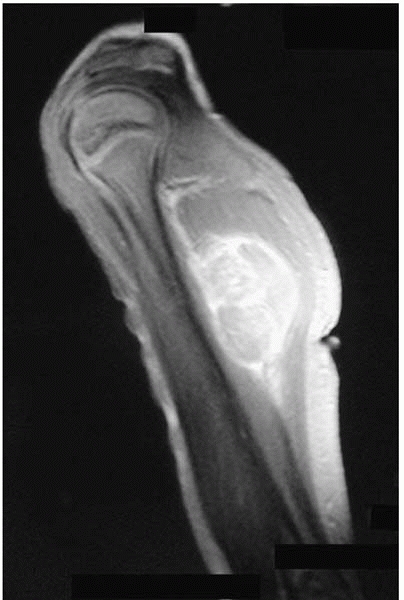

▪ FIGURE 17-12

This 4-year-old presented with a mass on her upper arm. The lesion was large, deep and hard, all signs that it could be a worrisome process. This MR image shows a large deep lesion that proved to be a rhabdomyosarcoma on biopsy. |